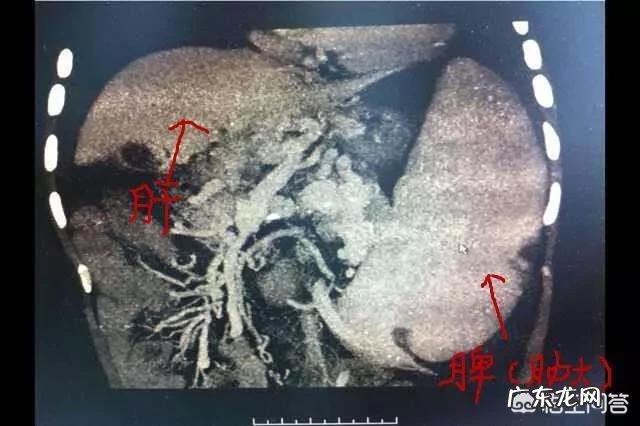

单纯的乙肝 , 哪怕是重症肝炎 , 一般来说也是不会有脾肿大的 。乙肝一旦出现脾肿大 , 可能预示着有肝硬化的趋势 。当然 , 脾肿大还有其他的原因 , 比如说EB病毒感染、伤寒等病 , 也会出现脾肿大 。

最重要的并发症之一是脾脏肿大 。肝硬化导致血管活性物质的增加和门静脉高压一起 , 加重了内脏的淤血 。脾脏是一个血窦 , 淤血表现得更为明显 , 久而久之就形成了脾肿大 。其他脏器 , 也有类似脾脏淤血的情况 , 主要表现为静脉曲张 。

所以 , 脾肿大的出现 , 不代表一定有肝硬化 , 但却是内脏充血的一个信号 。脾肿大的原因 , 在排除心血管系统等疾病后 , 一般和肝脏关系最密切 , 尤其是跟乙肝肝硬化的关系最密切 。